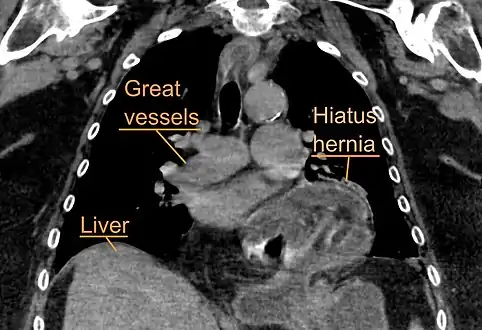

A hiatal hernia as seen on CT

A large hiatal hernia as seen on CT imaging

A large hiatal hernia as seen on CT imaging- As seen on ultrasound[9]